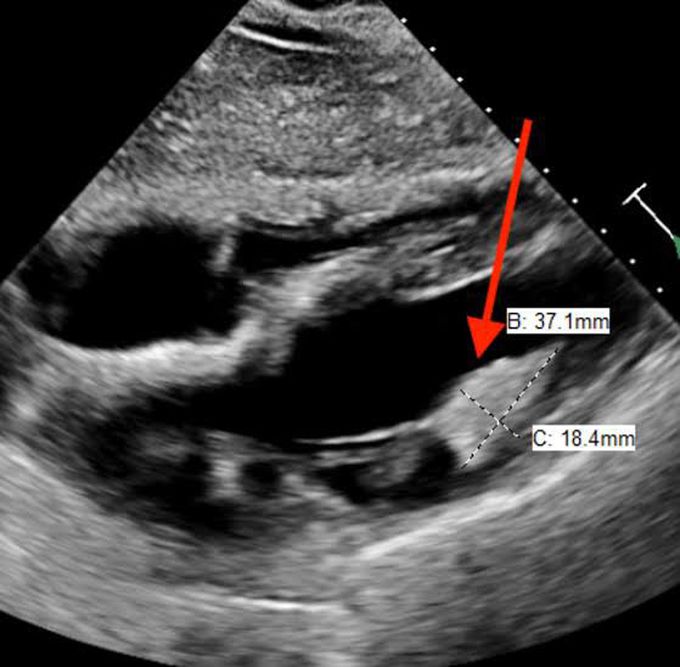

Rhabdomyoma

A rhabdomyoma is a noncancerous (benign) tumor that typically grows in clusters in the heart. Rhabdomyomas are the most common type of cardiac tumors seen in infants and children. Cardiac rhabdomyomas usually grow in the muscles of the left and right ventricles (the lower chambers of the heart).